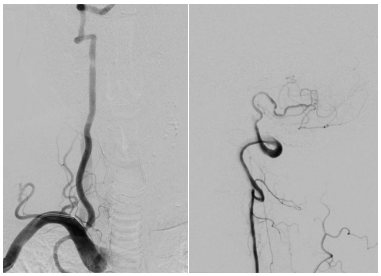

患者高先生,70岁,患有高血压病多年。2年前曾行冠状动脉搭桥术,平素规律服药。2个月前,他因左上肢突然麻木被送至清华大学垂杨柳医院急诊科就诊。头颅CT提示右侧顶叶少量蛛网膜下腔出血。后入住神经外科进一步诊治,全脑血管造影(DSA)结果显示:右侧椎动脉起始部重度狭窄约70%,左侧椎动脉颅内段闭塞;右侧椎动脉颅内段存在直径约3.5×2毫米的夹层动脉瘤;右侧颈内动脉颅外段存在重度狭窄,左侧颈内动脉通过前交通动脉代偿。

▲右侧椎动脉起始重度狭窄左侧椎动脉颅内段闭塞

▲右侧椎动脉V4段夹层动脉瘤